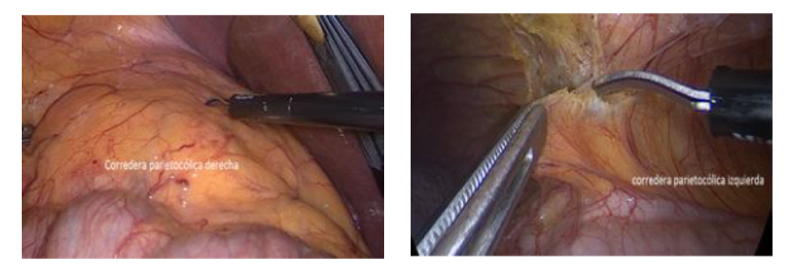

Para el abordaje transperitoneal hacemos una distinción entre el lado derecho e izquierdo. Para el lado izquierdo es necesario movilizar el colon descendente incluyendo el ángulo esplénico para exponer ampliamente la Gerota. En el lado derecho, por el gran espacio que deja la corredera parietocólica, pudiera no ser necesario movilizar el colon ascendente. En este caso escindimos directamente el peritoneo y Gerota como un sólo cuerpo, llegando directamente al riñón (Figura 24).

La dificultad que presenta este acceso directo es que el hilio de diseca desde el seno renal, con un mayor riesgo de provocar una lesión vascular. Para quienes tienen una menor experiencia, es recomendable hacer el camino largo, pero más seguro que es decolar el colon derecho, ubicar el plano entre la Gerota y el músculo psoas lumbar y abordar el hilio tal como fue descrito para la nefrectomía radical.